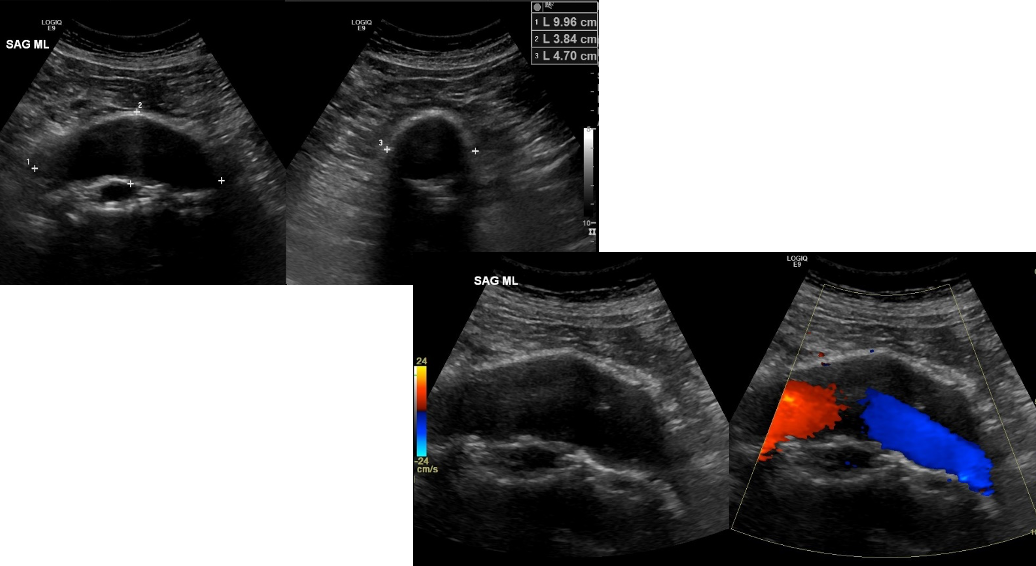

Which of the following matches with the findings below?

neoplastic IVC obstruction